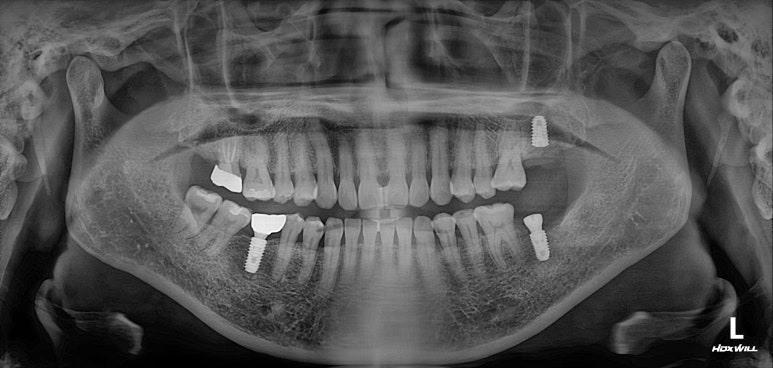

딱 봐도 치아가 조금 없는 것 같으시죠?

빨간색 동그라미로 표시된 곳에 치아가 없어요! 왼쪽 아래 두번째 어금니를 뽑으신 지 몇 년 지나신 상태였습니다.

노란색 동그라미로 표시된 치아는 뿌리만 있는 잔존치근 상태로, 살릴 수 없는 치아였어요.

그리고 마지막으로 파란색 동그라미로 표시된 치아는 기존 크라운 아래로 이차충치가 생겨서 신경치료가 필요한 상태!

아래턱 사진을 보시면 치아가 하나 비어있는 것을 아실 수 있죠? 두 개 비어보이시겠지만, 하나는 사랑니니깐 한개로 칩니다. 아까 치과용 파노라마에서 빨간색 동그라미!

위턱 사진을 보시면 뿌리만 있는 치아를 확인하실 수 있을거에요. 노란색 동그라미!

마지막으로 딱 한개 있는 금니를 보실 수 있을텐데, 이차 충치가 있어 다시 치료해야했던 치아입니다. 파란색 동그라미!

임플란트 또한 적절히 유지되고 있고 잘 사용하고 계신 상태입니다.

신경치료와 지르코니아 크라운 치료를 받았던 치아도 뿌리끝 염증 없이 잘 사용중이시구요!

치아가 없던 자리에 자연스러운 흰색의 지르코니아 크라운을 갖는 임플란트가 생겼고,

이차 충치가 있던 금니도 새로이 제작된 지르코니아 크라운으로 잘 사용하고 있으신 상태입니다.

사랑니가 없어져 더욱 개선된 구강위생관리도 확인할 수 있었습니다!